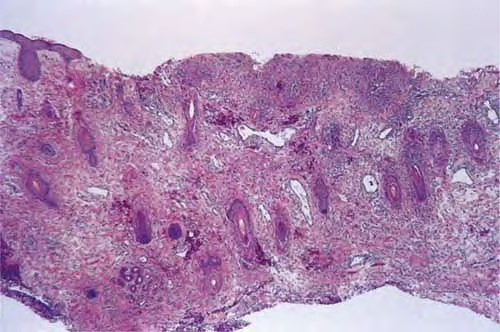

Herpes simplex = العقبول البسيط